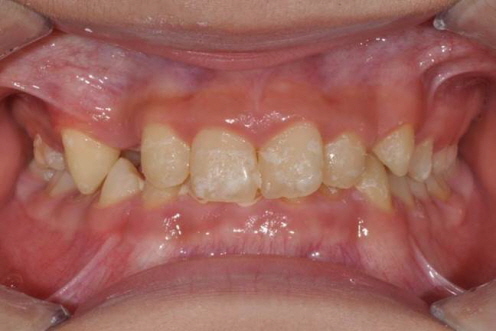

아래턱이 작고 앞니끼리 너무 깊게 물린 케이스입니다. 과개교합교정을 통해 정상교합을 만들었습니다.